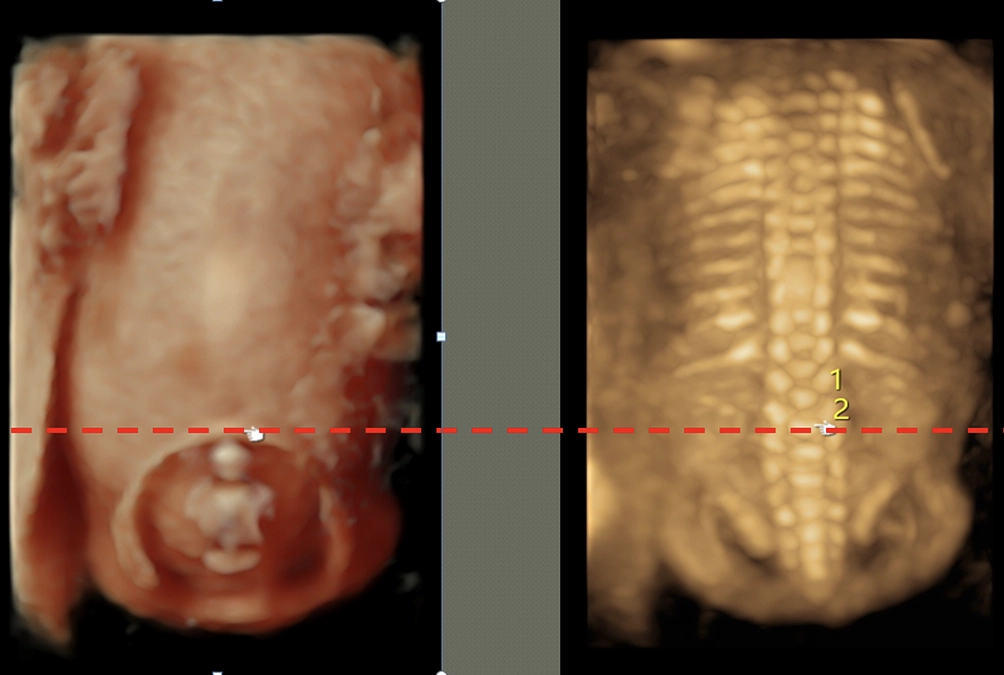

2019年6月初旬に、大阪大学の胎児治療プロジェクトチーム4名(産婦人科医 遠藤、小児外科医 渡邊、脳神経外科医 香川、手術部看護師 千賀)で、脊髄髄膜瘤胎児手術の手術見学にアメリカ・ペンシルベニア州のフィラデルフィアにあるフィラデルフィア小児病院へ手術見学に行ってきました。

CHOPには、小児外科医のDr.Adzickが率いる胎児診断治療センターがあり、胎児治療の分野で世界をリードしています。2011年に、ここで脊髄髄膜瘤胎児手術の有用性が証明されました。